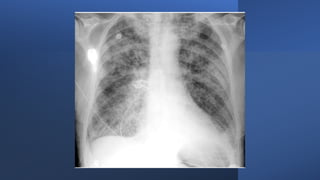

Imaging tests

X-ray.

X-rays can identify infections in

lungs.

Pneumonia can be confirmed by a chest X

ray showing new shadowing that is not

due to any other cause (such as

pulmonary oedema or infarction).